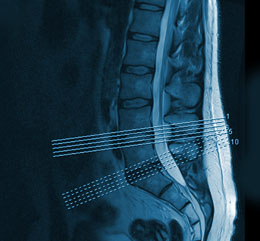

MRT-Diagnostik

Die MRT-Diagnostik ist aus der modernen Medizin nicht mehr wegzudenken.

Ohne das Risiko einer Strahlenbelastung erhalten wir äußerst präzise Bilder des Körperinneren und können so Krankheiten besser erkennen.

Für Privatpatienten führen wir MRT-Untersuchungen an einem Standort außerhalb der Praxis regelmäßig selbst durch. Hierfür ist ein Arzt aus unserer Praxis vor Ort anwesend und wird das Ergebnis direkt im Anschluss an die Untersuchung mit Ihnen besprechen.